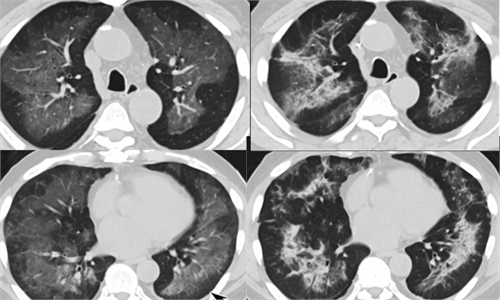

It's possible that some of the patients of the mysterious vaping-related lung disease that swept through all of the 50 US states in 2019 were actually COVID-19 patients, according to ...